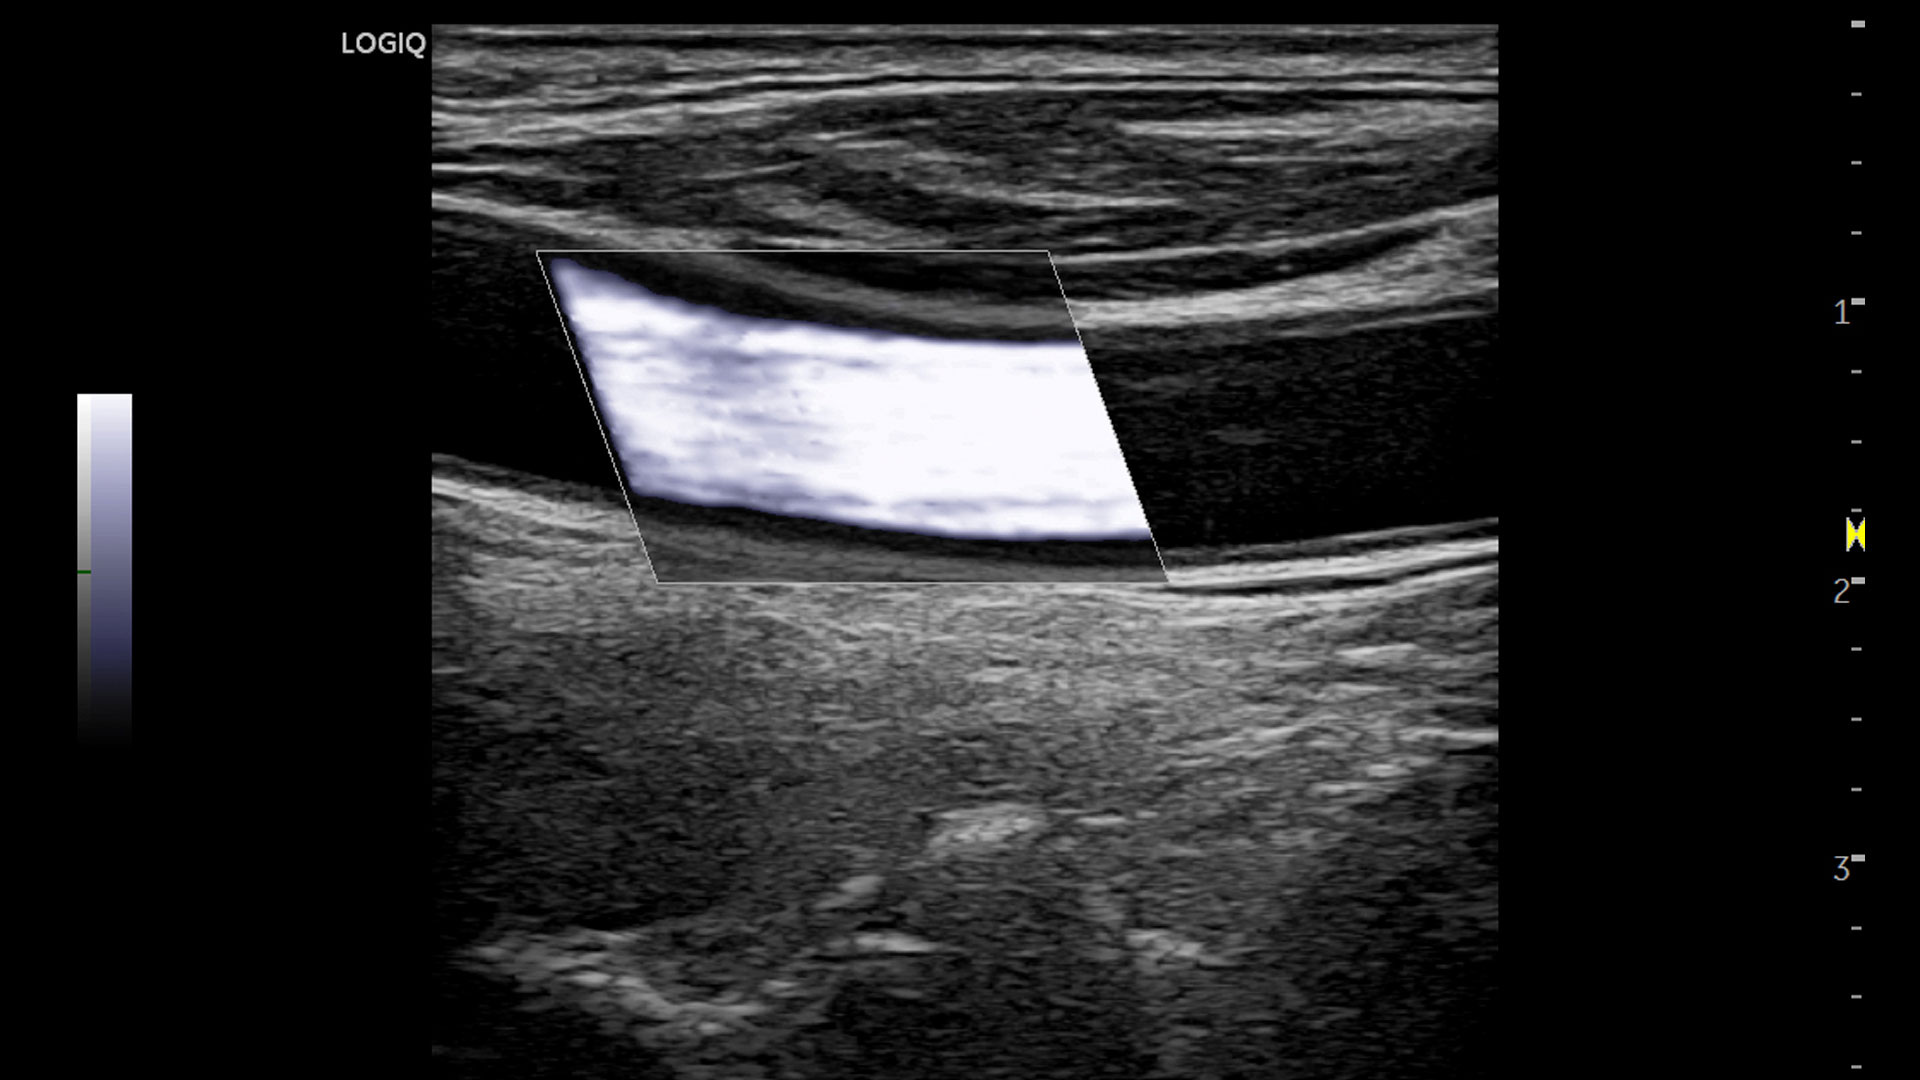

LOGIQ™ P Series

Personalized workflow tools and automation, for efficiency. Expanded patient-centric diagnostic capabilities, for flexibility. And powerful support, for long term value.

LOGIQ P Series ultrasound brings you advanced ways to increase everyday efficiency—tools and functions you can customize to your own preferences so exams flow easily, your way. Plus access to industry-leading cybersecurity, data management, and educational resources to help you optimize system uptime and utilization, while enhancing user skills.

Expanded patient-centric diagnostic capabilities for flexibility

Manage simple to complex cases with the LOGIQ P Series.

Multi-purpose capabilities, including liver, cardiac, OB/GYN, vascular, breast, thyroid, musculoskeletal, urologic, and pediatric studies.

Superb image quality with XDclear probes: Powerful high fidelity and broad bandwidth produce high resolution images whether scanning superficial or deep targets.

Advanced imaging and visualization tools, including:

• 2D Shear Wave Elastography

• Ultrasound-Guided Attenuation Parameter (UGAP)

• CEUS

• B-Flow and B-Flow Color

• 3D/4D with SonoRenderlive

• Stress Echo